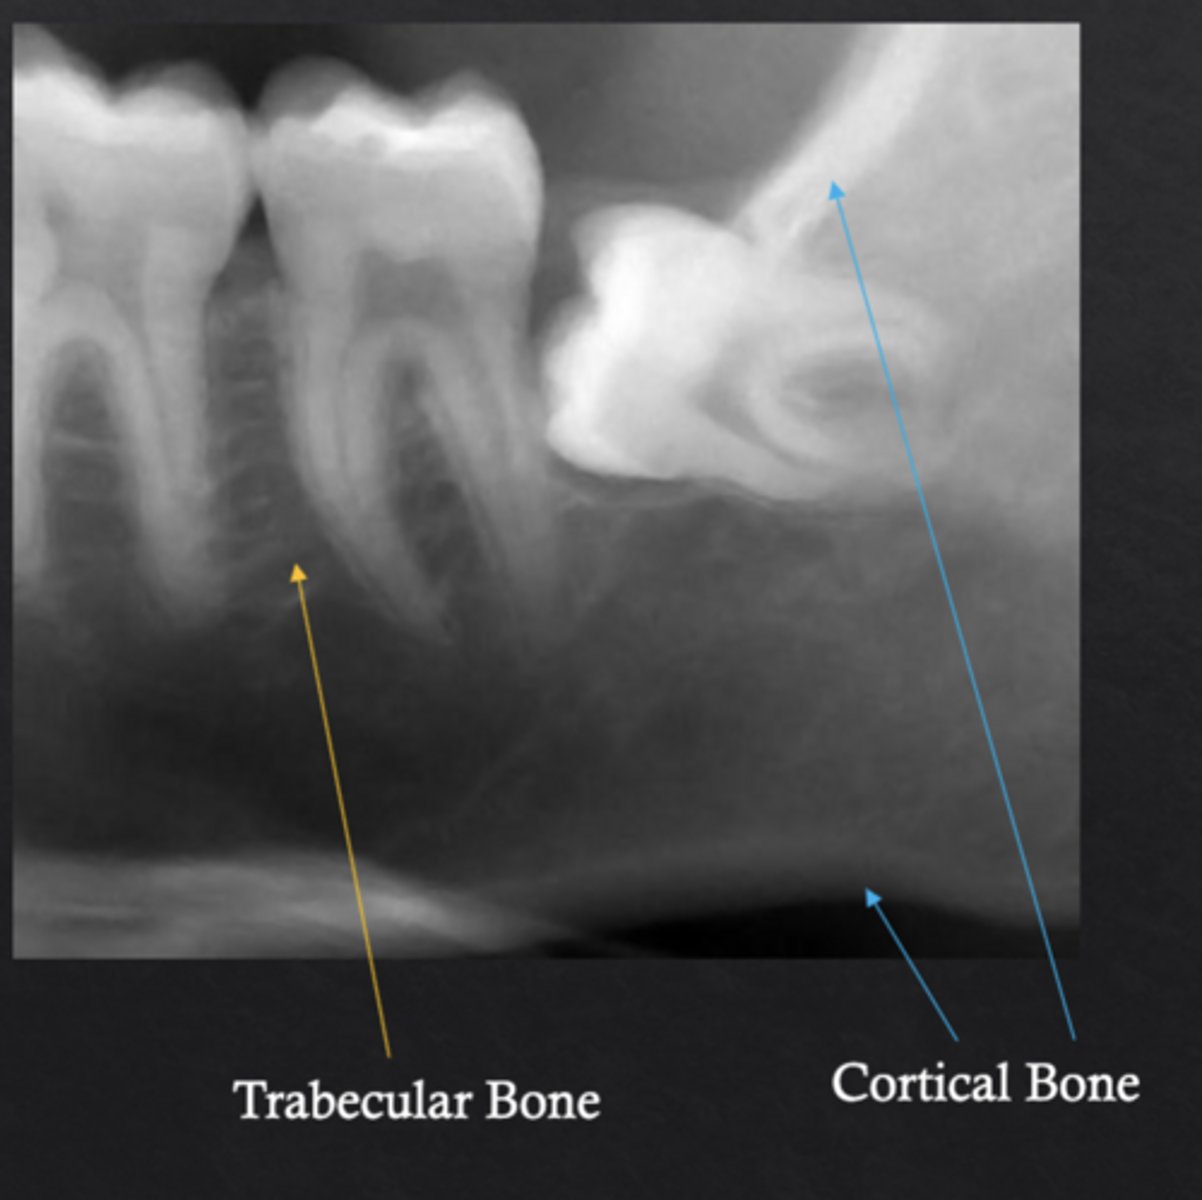

What are the two major structural types of bone?

Cortical bone and trabecular (cancellous) bone

What is cortical bone?

Dense outer bone layer that provides structural strength

What is trabecular bone?

Spongy inner bone composed of trabecular networks and marrow spaces